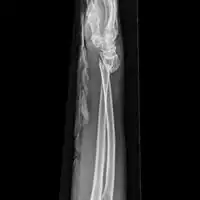

Front view of displaced fractured radius and ulna at wrist -

Side view of displaced fractured radius and ulna at wrist -